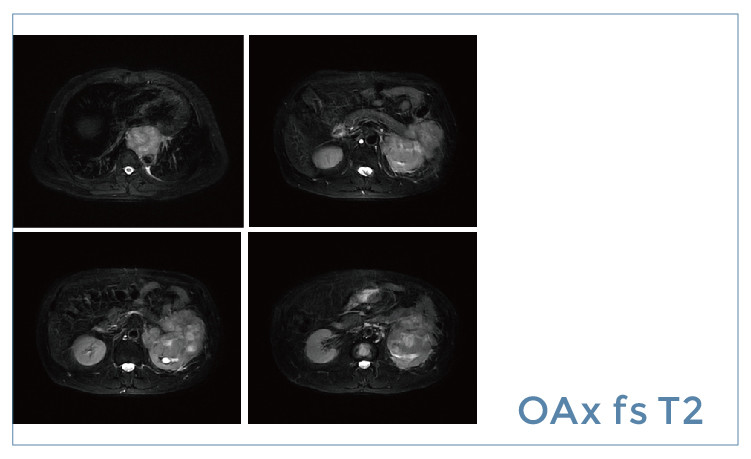

【朗润影像档案】磁共振影像病例分享(编号20190419)

【朗润影像档案】20190419磁共振影像病例结果讨论